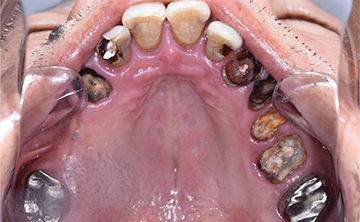

虫歯を放置して3年経って来院された患者さんです。噛めなくなったが主訴です。虫歯が進行しているのも確かですが、歯石も多く付着していますね。虫歯の中にオレンジのものが見えていますが、これは、根の治療後に詰める防腐剤ですね。

根の治療をすると歯に痛みを感じなくなるので、虫歯が進行しても痛みを感じずに歯冠崩壊を招きます。できるだけ歯の神経を取らない方が良いですが、虫歯が歯の神経に近く痛みが出る場合は、虫歯の歯の神経治療が必要になります。

非常に素晴らしい患者さんで、この後、しっかりと通って虫歯を全て治して、噛める状態にまで回復しました。